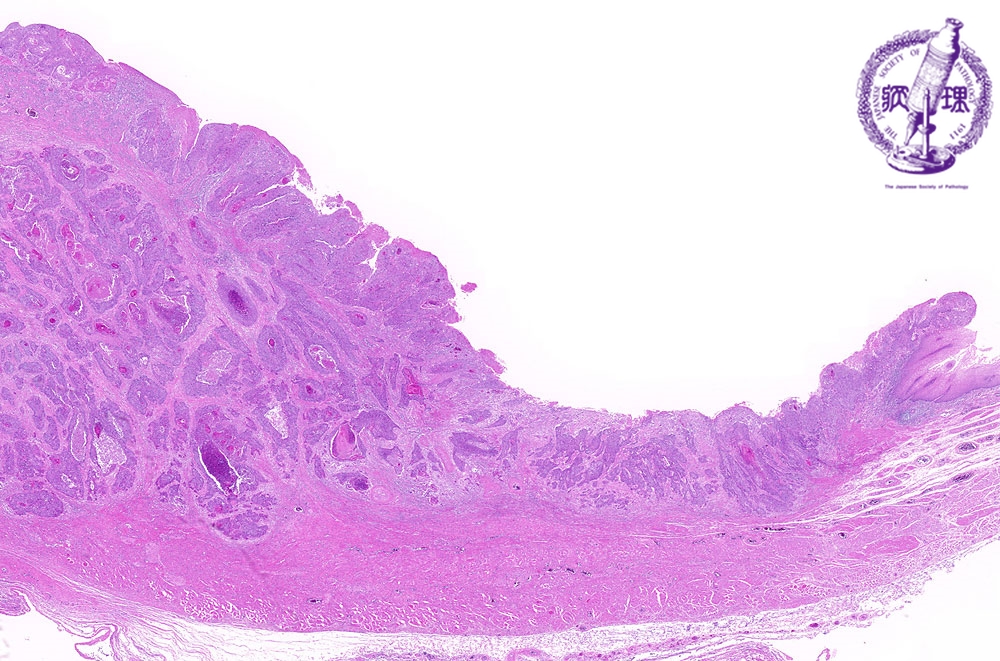

- ★(3)Esophageal carcinoma (squamous cell carcinoma)

Microscopic view (H&E stain, low power): There is squamous cell carcinoma invading into the muscularis propria (arrow: boundary between normal mucosa and carcinoma, dotted line: invasion into the muscularis propria).